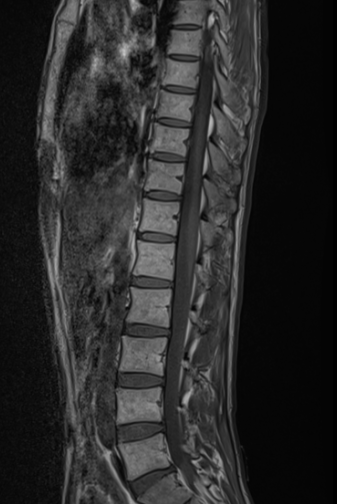

척추 mri를 찍어서 봤는데 저런식으로 홈이나 금간것저럼 보이는게 있는데 저건 뭔가요???

뼈에 금이 간게 아니라면 뭔지 궁금합니다

• 1번 째 사진

이런 경우에 골절이 아닌지 오해하시는 경우가 많은데 골절이 아닙니다.

골절의 경우에는 T1 영상에서 조영이 떨어지고 fat suppression T2 영상에서 조영이 증가하는 소견을 확인해야합니다.

골절이 아니면 왜 저렇게 보이는지 까지는 제가 잘 모르지만 저 소견을 이상소견으로 보이는 않습니다.